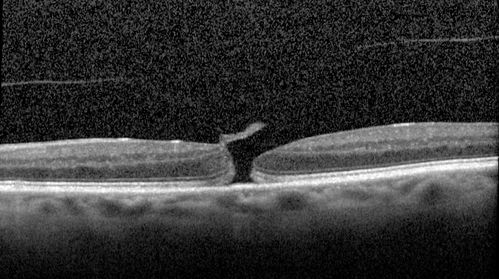

Stage II Macular Hole - PPV without ILM peel

77 year old man with 20/40 VA on presentation. Macular hole did not abort and vision dropped to 20/63. Post PPV vision was 20/25 within 6 months